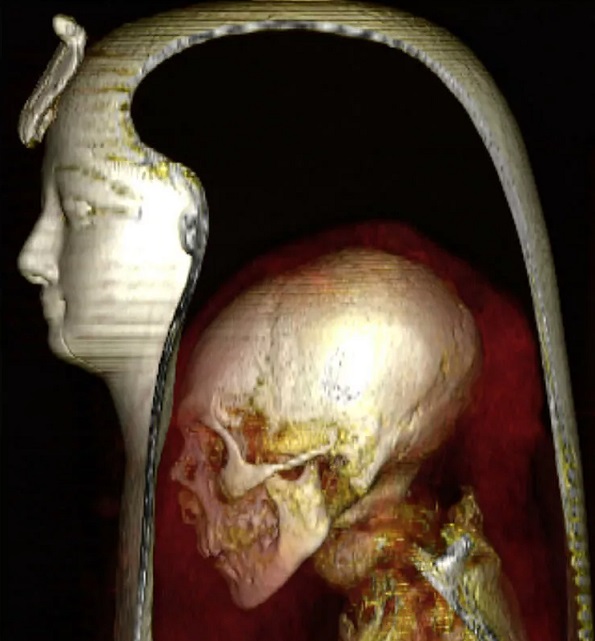

Мумию фараона Аменхотепа I рассмотрели с помощью компьютерной томографии

Ученые развернули фараона Аменхотепа I, который правил с 1525 по 1504 год до нашей эры, с помощью компьютерной томографии.

Ученые развернули фараона Аменхотепа I, правившего с 1525 по 1504 год до нашей эры, с помощью цифровой компьютерной томографии. Это единственная королевская мумия, оставшаяся нераспечатанной в наше время. Сканирование показало, что фараону было 35 лет, его рост 169 см и находился в хорошем физическом состоянии, когда умер. Его смерть, скорее всего, произошла от естественных причин.

В исследовании, опубликованном в журнале Frontiers in Medicine, ученые описали внешний вид, состояние здоровья, причину смерти и стиль мумификации королевской особы. Они исследовали мумию с помощью компьютерной томографии и сгенерировали двух - и трехмерные изображения маски для головы, бинтов и практически развернутой мумии.

Распечатав цифровую упаковку королевской мумии, ученые обнаружили, что он внешне напоминал своего отца: узкий подбородок, маленький узкий нос, вьющиеся волосы и слегка выступающие верхние зубы. Ученые заявили, что они не смогли найти никаких ран или увечий из-за болезни, чтобы узнать точную причину смерти, за исключением многочисленных посмертных увечий, предположительно нанесенных грабителями могил. При мумифицировании его внутренние органы были удалены, но мозг и сердце оставлены на месте.